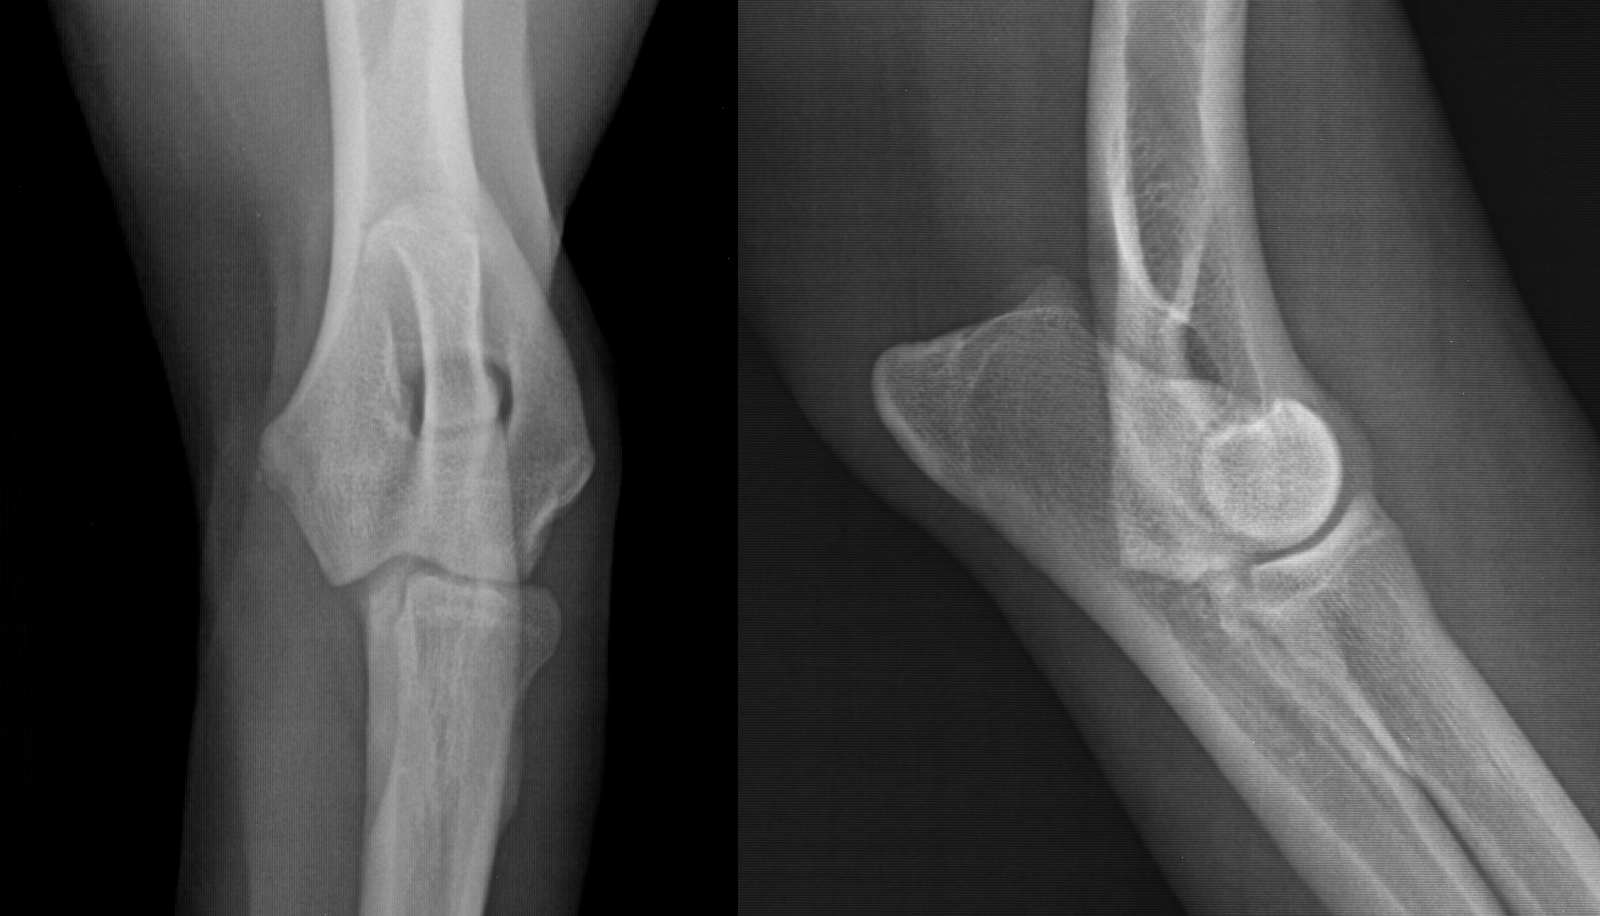

Bei der ausführlichen Lahmheitsuntersuchung seiner Vordergliedmaßen ging ich wie üblich systematisch vor, testete seine Reflexe und ließ kein Gelenk aus. Am linken Ellbogen wurde ich fündig und konnte eine Abwehrreaktion bei der Streckung und der sogenannten Coronoidprobe provozieren. Eine positive Coronoidprobe bedeutet, dass der Patient auf die Rotation der Gliedmaße mit Schmerzen im Ellbogen reagiert. Zum Vergleich untersuchte ich auch die gegenüberliegende Gliedmaße, an der „Oscar“ an keinem der Gelenke reagierte. Da meine orthopädische Untersuchung auf eine Ellbogenerkrankung hinwies und die bisherigen Röntgenaufnahmen der Ellbogen aufgrund der Überlagerung mehrerer Knochen keinen eindeutigen Befund ergaben, empfahl ich die computertomographische Schnittbilduntersuchung (CT) beider Ellbogengelenke.

Zusammenfassend möchte ich sagen, dass die Computertomografie aus der modernen tiermedizinischen Diagnostik nicht mehr wegzudenken ist. Insbesondere werden, wie bei „Oscar“, frühe Anzeichen einer Ellbogengelenkdysplasie im Röntgen oft übersehen, die im CT zweifelsfrei darstellbar sind. Da eine unbehandelte Ellbogendysplasie meist zu schweren Arthrosen führt, empfehlen wir beim lahmenden Jungtier eine möglichst frühzeitige computertomographische Diagnostik und entsprechende Therapie, noch bevor es zu irreparablen Schäden am Gelenk kommen kann.